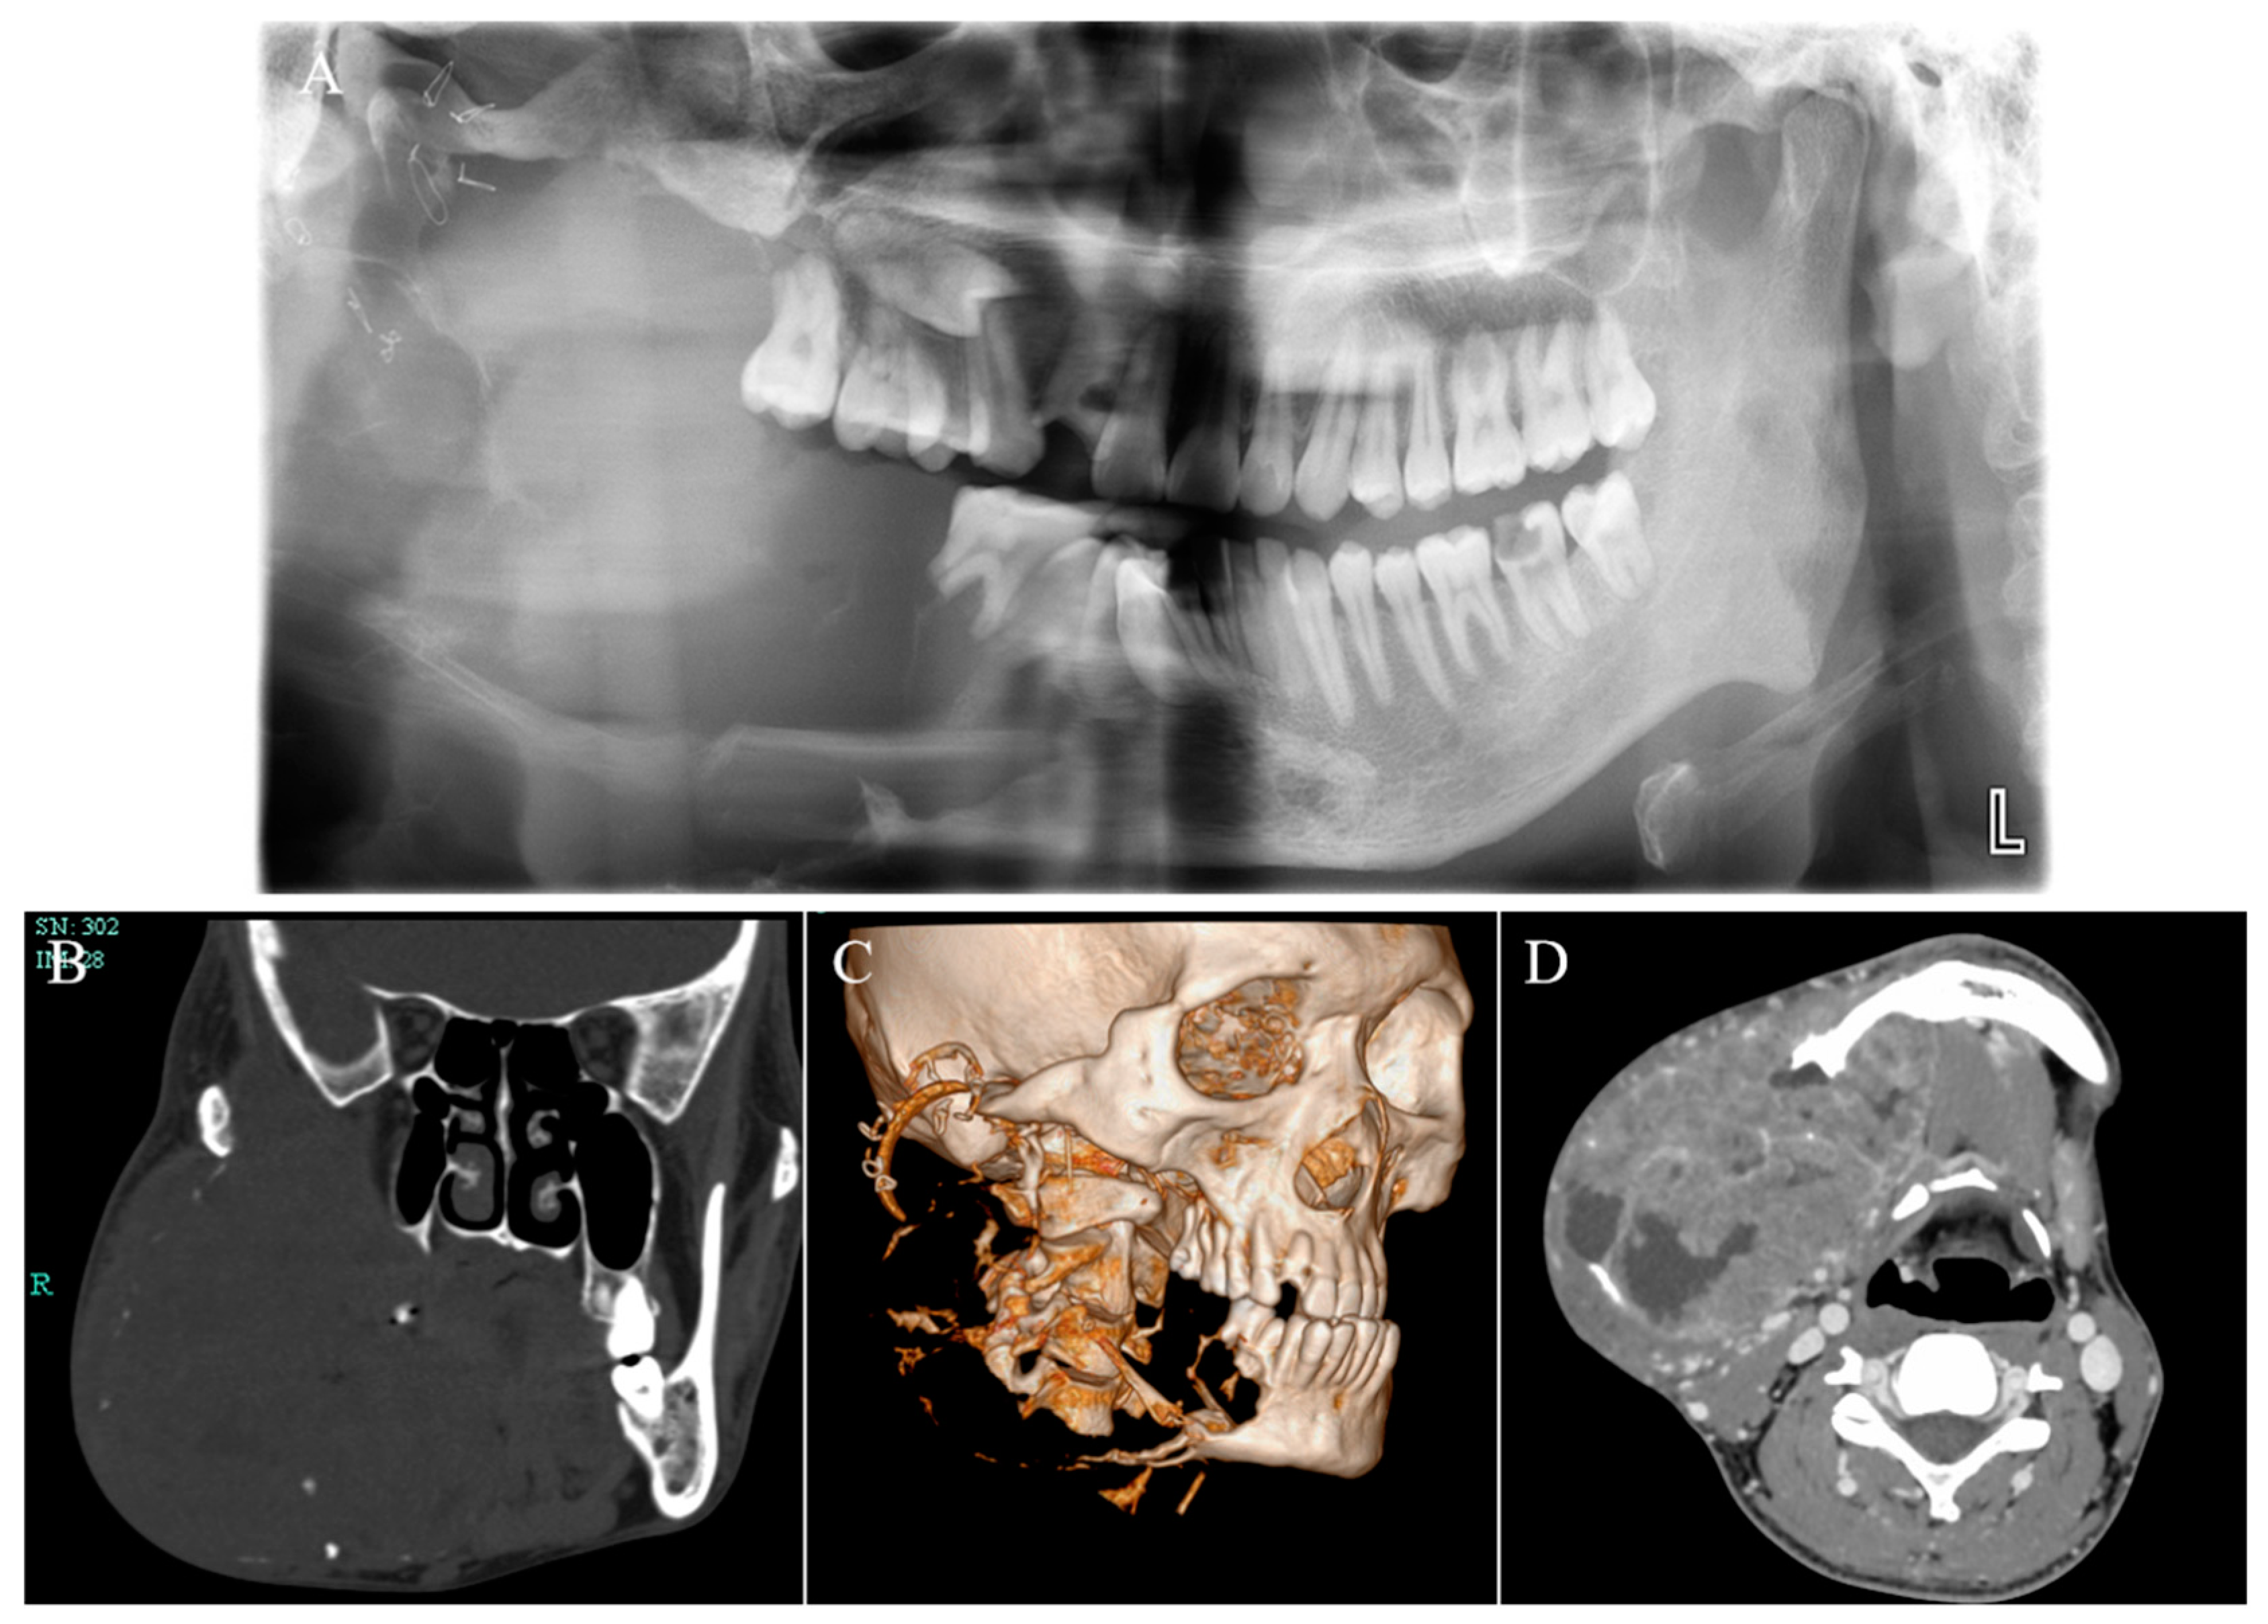

One year after marsupialization, the patient was referred to our hospital urgently due to his progressively serious condition. During the first physical examination, the patient was malnourished, weak, and exhibited cachexia (BMI = 16). Specialized examination revealed a huge swelling in the right mandible causing significant facial asymmetry (Figure 2A,B). On palpation, the mass exhibited as fixed, ill defined, non-fluctuant, and non-tender. The right buccal vestibule and gums were affected intraorally by this enlargement, appearing widely swollen with a cauliflower-like mass (Figure 2C). This mass was prone to bleeding, and yellow pus was observed when squeezed (infection). There was no cervical lymphadenopathy or symptoms of distant metastases. Panoramic radiography, CBCT, and MRI imaging showed extensive bony destruction of the right mandible with a huge soft tissue mass, measuring 7.3 cm × 9.5 cm (Figure 3). The lesion involved the right cheek muscle and extended upward to the right palatal fossa, and the posterior lateral wall of the right maxillary sinus was also absorbed and destroyed.

Figure 3.

Panoramic radiography (A), CT (B), three-dimensional reconstruction (C), and MRI (D) showed an expansive growth pattern of the tumor with bony destruction and huge soft tissue mass.